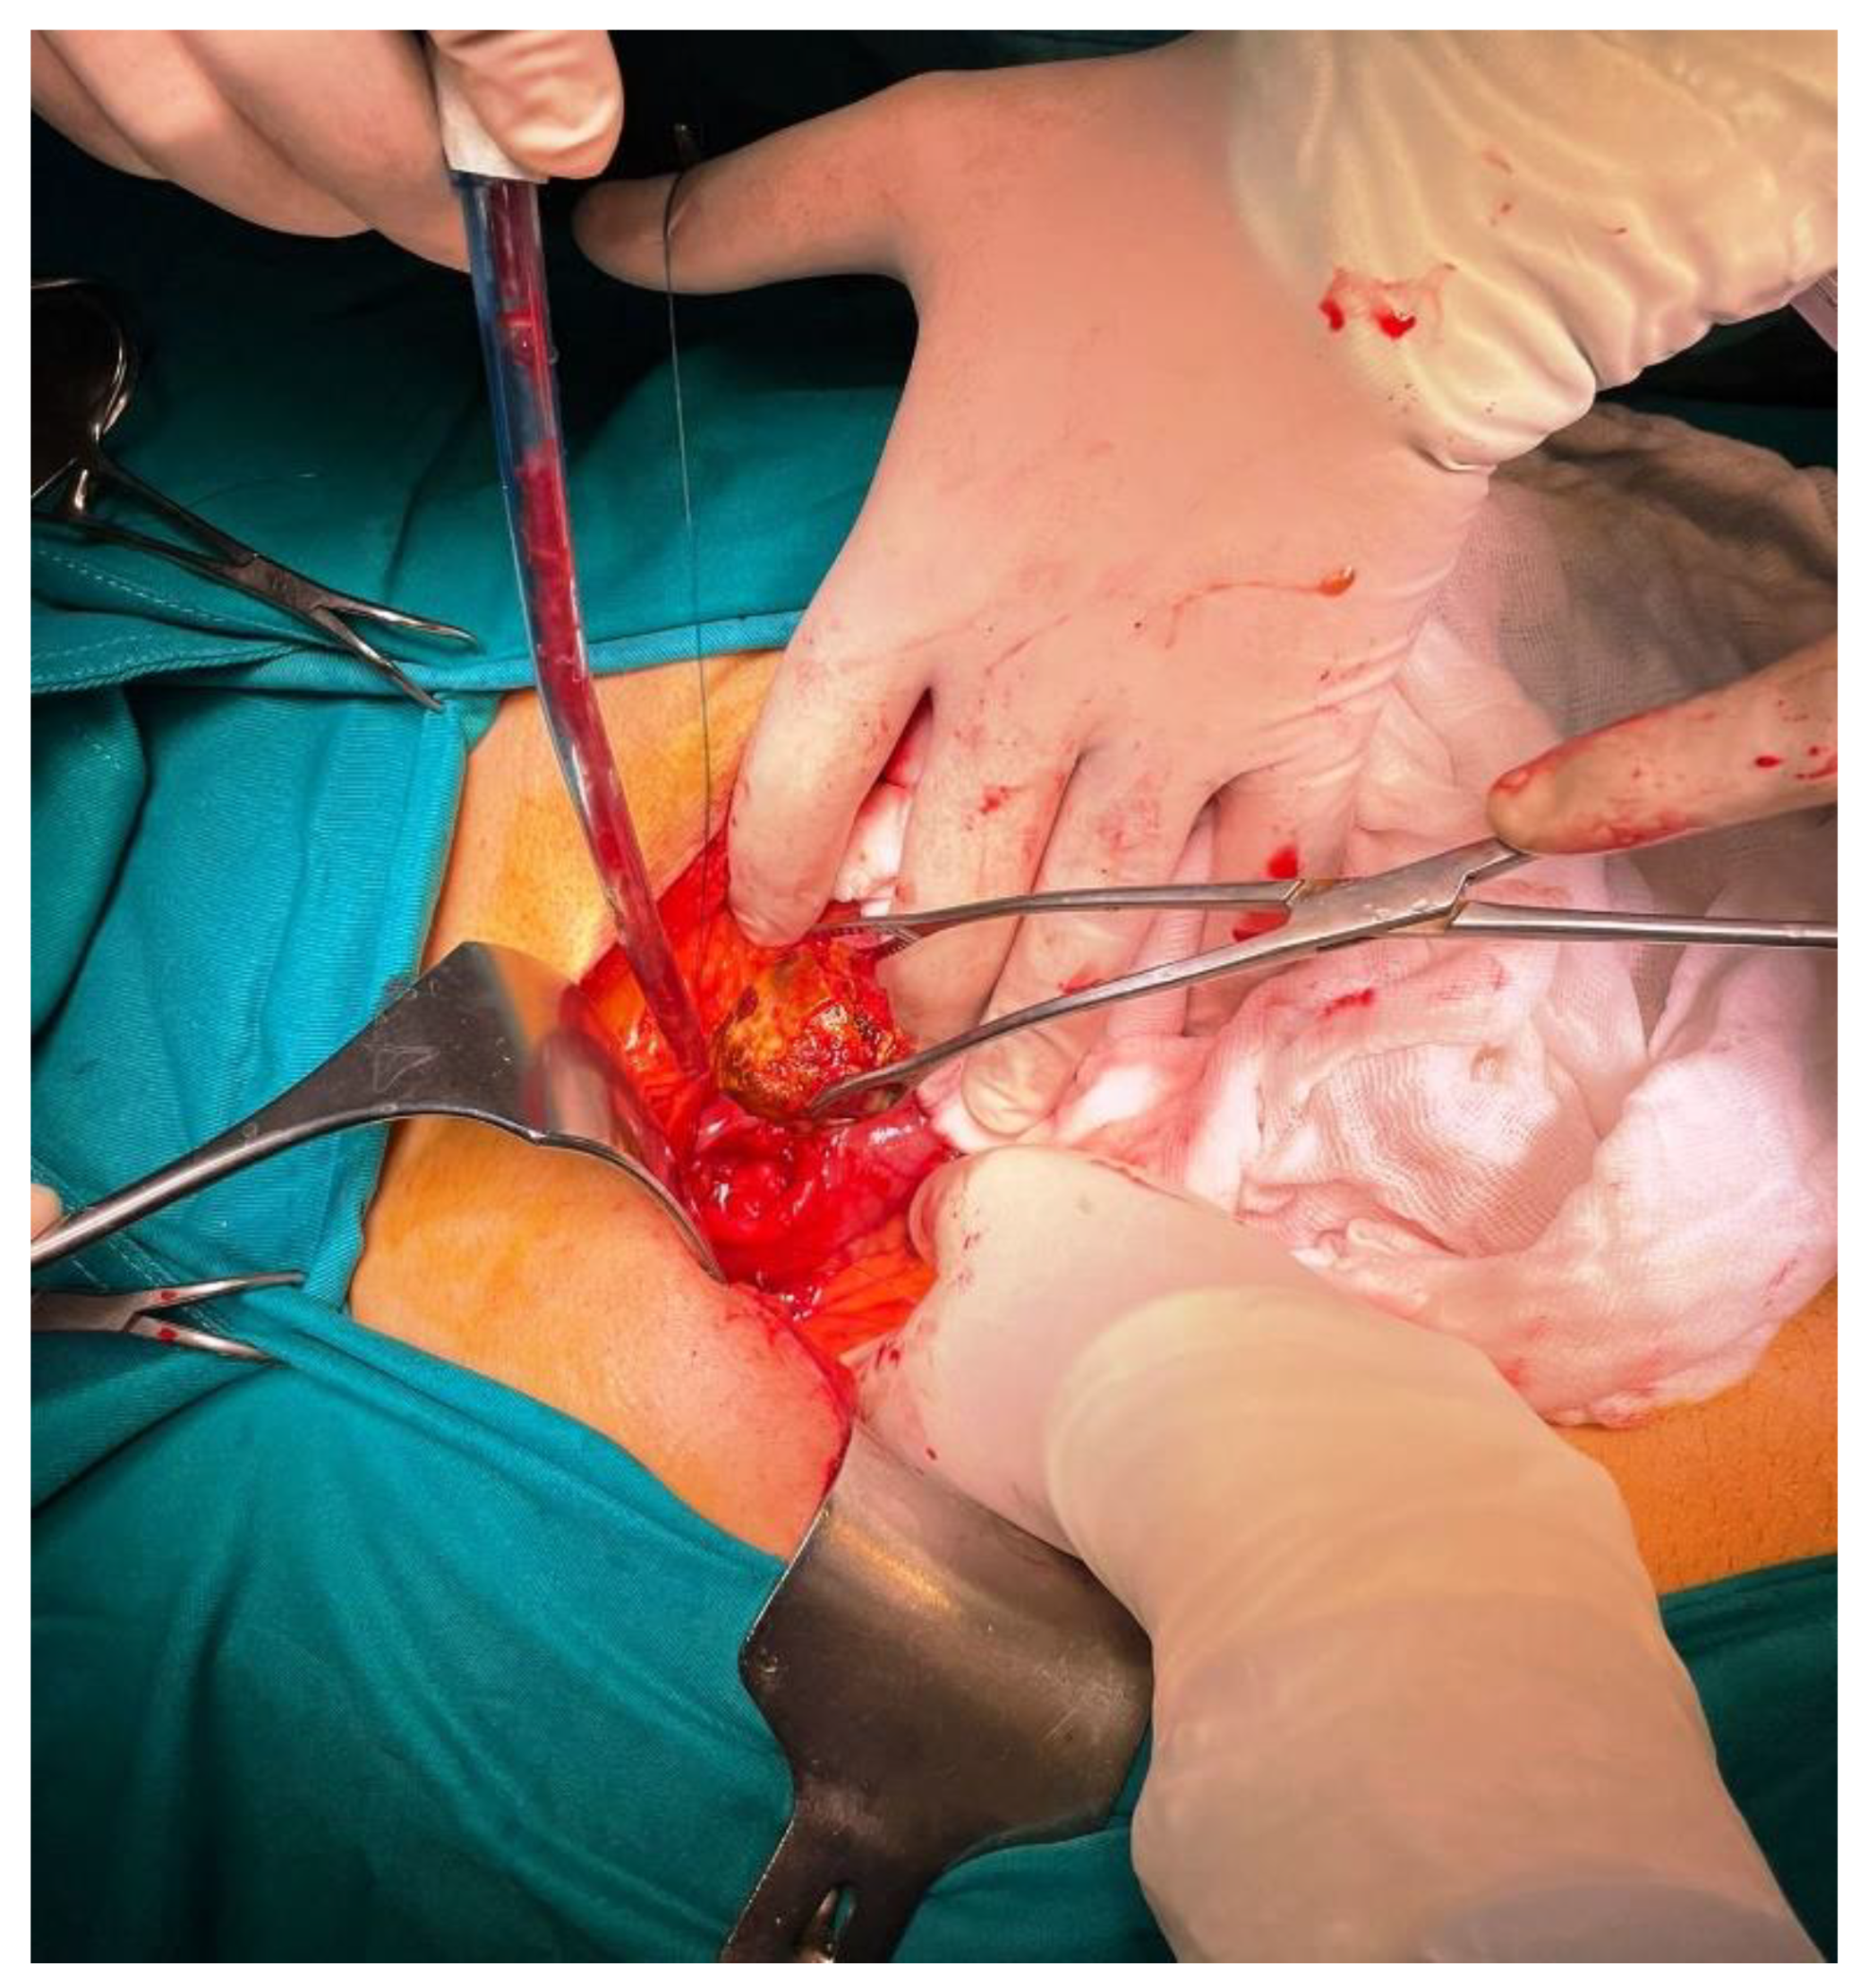

Figure 7, Figure 8 and Figure 9 Patient immediately have been treated by open surgery including gallstone extraction, gastrotomy, duodenal suture and cholecystectomy (Figures 7,8,9). Both parenteral nutrition and antibiotics were introduced during the postoperative period so patient was discharged after 7 days. Enterotomy or gastrotomy with or without cholecystectomy and fistula repair remains the treatment of choice. It has high success rate, with acceptable surgical morbidity and mortality [11]. It is still a matter of debate whether cholecystectomy and repair of the fistula should be performed, due to spontaneous closure of fistulas in some cases [9,12,13]

Figure 7. Intraoperative findings.

Preprints 107205 g007

Figure 8. Intraoperative findings.

Preprints 107205 g008

Figure 9. Intraoperative findings.

Preprints 107205 g009